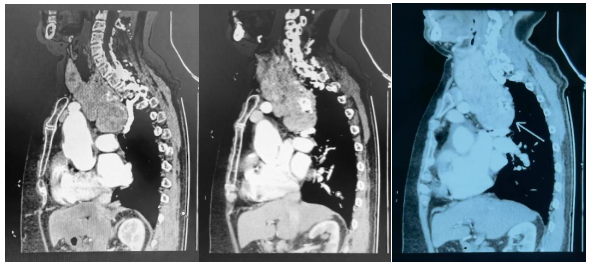

患者由于肿瘤长期压迫心包和肺动、静脉,已经出现心包积液,并伴有严重的房颤、三尖瓣重度反流、肺炎。哈医大肿瘤医院头颈外科鼻咽喉口腔二病房项丞教授经过专业判断,发现肿瘤的来源是甲状腺,虽然颈部的包块并不明显,但肿瘤向下生长,从颈部一直长到胸部,成为了“压在心里的大石头”。

经过充分的术前讨论和准备,由项丞教授团队为患者实施手术。医疗团队全神贯注,手术器械在锁骨下动脉、头臂经脉、上腔静脉、肺动脉干、主动脉弓表面徐徐推进,肿瘤一点一点从胸腔升起。跳动的心脏使得手术区域不停的上下起伏,项丞教授顺应着心脏收缩、舒张的节律调整团队手术操作的节奏,把分离肿瘤对心脏的影响减到最低,肿瘤主体终于从胸腔逐渐“浮出水面”。整个肿瘤完整的从颈部和胸腔内取出。患者的气管、心脏和各大血管终于解除压迫、回归正常位置。